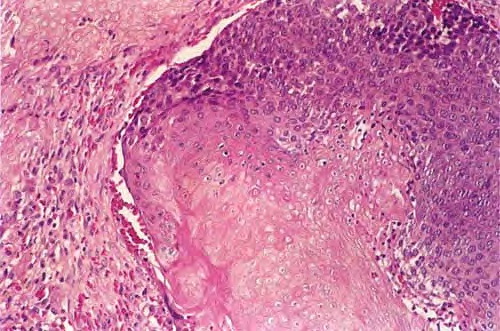

Pilomatricoma shows a spectrum of morphologic features that mainly reflect different evolutionary stages. Early and well-developed pilomatricomas reveal variably sized, round to oval cystic lesions lined by a basaloid epithelium at the periphery and filled in the center with masses of eosinophilic, faulty hair matrix material containing “shadow” (“ghost”) cells

Basaloid (matrical) cells show monomorphous round nuclei with one or more distinctive nucleoli and variable numbers of mitotic figures. Foci of squamoid epithelium are sometimes noted within the epithelial lining. Regressing pilomatricomas display haphazardly arranged foci of basaloid cells and shadow cells as well as an inflammatory infiltrate with multinucleated histiocytic giant cells. Granulation tissue is sometimes noted. Old pilomatricomas reveal no basaloid component but show irregularly shaped, partially confluent masses of shadow cells with foci of calcification or ossification. Melanin deposition, trans-epidermal elimination, and extramedullary hematopoiesis have been described in some pilomatricomas. A peculiar variant with relatively large areas of basaloid cells and small foci of shadow cells (“proliferating pilomatricoma”) is occasionally observed in older adults.